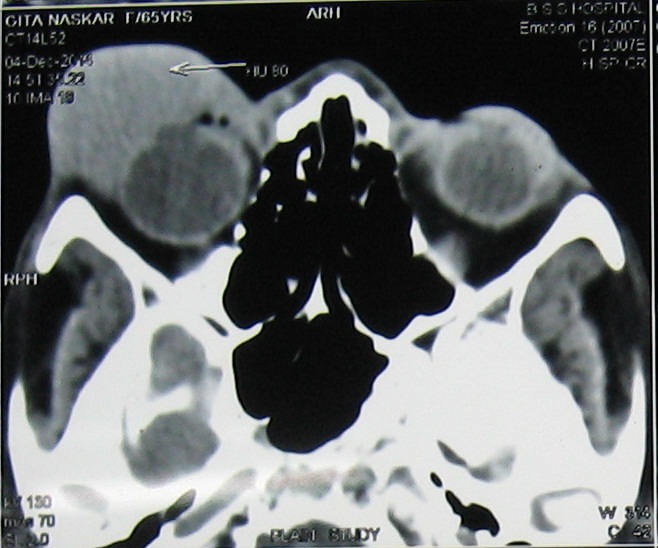

Primary Non-Hodgkins lymphoma of the orbit is a rare presentation and the diffuse large B-cell lymphoma (DLCL) type of histology is much less commoner than the mucosa associated lymphoid tissue (MALT) and follicular lymphoma. A 70 years female patient presented with palpable mass arising from right orbit and proptosis of the right eye. CT scan suggested homogenous enhancing soft tissue mass affecting right lacrimal region without any bony destruction. Biopsy confirmed it to be a case of Primary non-Hodgkins lymphoma of diffuse large B-cell type with strongly positive CD 20. She was given 6 cycles of chemotherapy with R-CHOP after surgery. The patient is now asymptomatic one year after the last cycle of the chemotherapy.